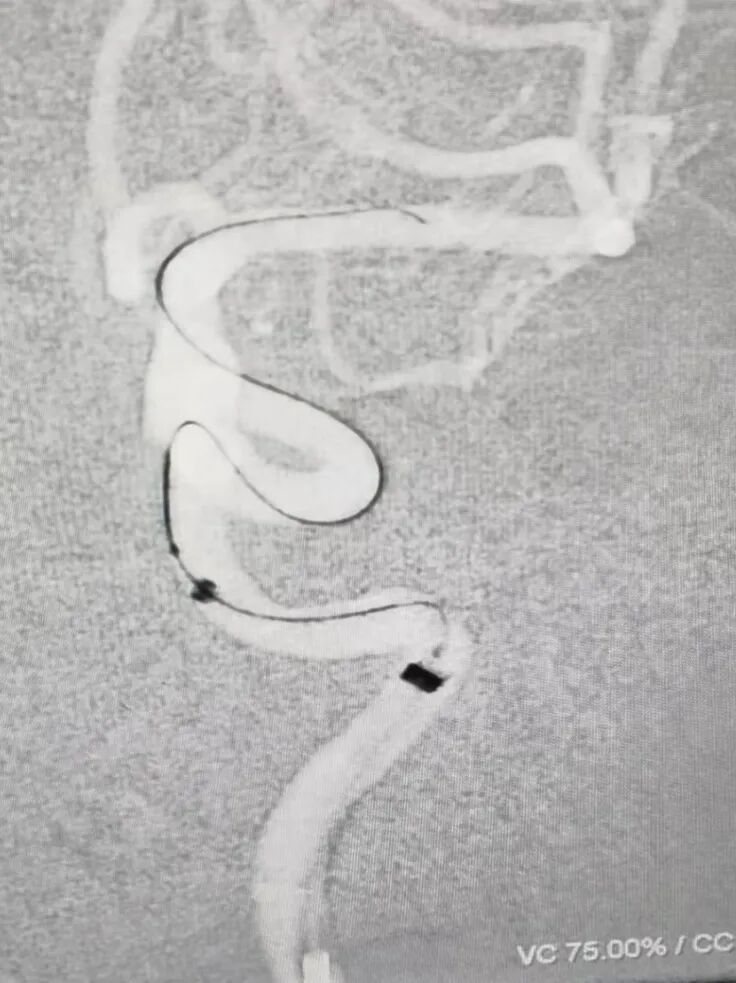

左侧颈内动脉:

Synchro 2导丝和X-T27同轴带CAT5到大脑中M1段远端。

左侧同样路径迂曲,海绵窦III型导致基础支撑不足,Surpass Streamline血流导向密网支架无法到位,至海绵窦段高到位,微导丝和CAT5送高,增强系统支撑,支架顺利跨过虹吸弯到位

动脉长鞘怎么置入术说·第十七期丨Infinity长鞘助力Surpass Streamline血流导向密网支架治疗双侧颈内迂曲路径动脉瘤一例_https://www.jmylbn.com_新闻资讯_第24张

退支架外鞘管,将Surpass Streamline血流导向密网支架先释放到CAT5里6-7mm。

再退CAT5到外鞘管以下2mm,让支架锚定于远端。但发现支架远端定位过高,覆盖了脉前动脉,遂用CAT5回收支架,重新定位后释放。

由于血管迂曲,支架推出困难,遂进行远端减张释放,推出支架后再增张,因此导致支架远端打开不良,用3.5*15mm Gateway球囊在支架远端扩张。

球囊扩张后再进行导丝按摩支架,工作位造影显示支架贴壁有所改善,动脉瘤内造影剂滞留明显。